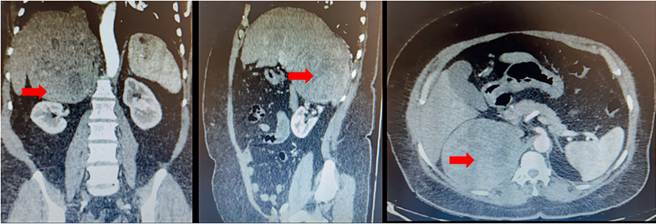

La ecografía abdominal informó una lesión sólida bien definida en espacio hepatorrenal, con ecogenicidad heterogénea, de 11 x 10 cm, en relación con tumor adrenal derecho (figura 1). La tomografía computarizada de abdomen simple y contrastada confirmó la presencia de una masa solida adrenal derecha, de 11 x 10,5 x 10,7 cm, de densidad heterogénea, con áreas centrales hipodensas por necrosis, que desplazaba y con efecto compresivo sobre la vena cava y renal derecha, y en estrecha relación con la arteria renal derecha aproximadamente a 1,8 cm de su origen, compatible con carcinoma adrenal cortical (figura 2). La resonancia nuclear magnética encontró además desplazamiento de la vena cava, hígado y riñón derecho sin invadirlos, áreas necróticas y una fuerte adherencia a la fascia pararrenal posterior derecha.